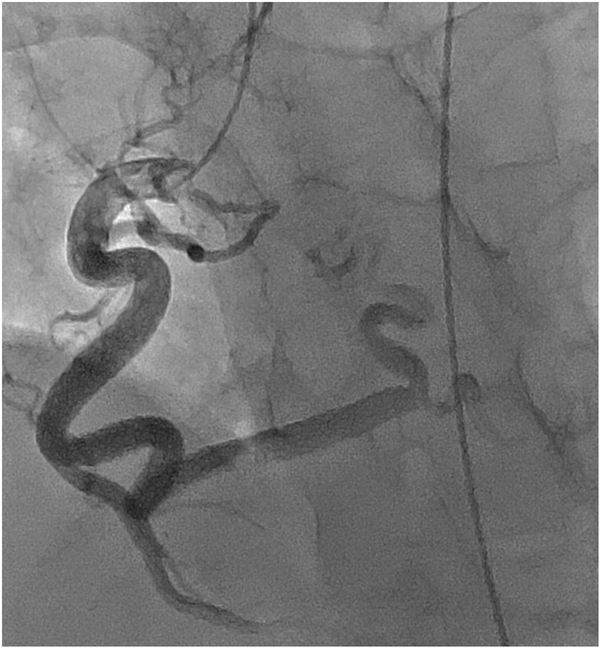

冠動脈でも同様に血管の拡張・蛇行,新生血管の増生がみられるが,冠血流予備能は低下する(図4, 5).

Pediatric Cardiology and Cardiac Surgery 31(3): 95-101 (2015)

図4 左冠動脈の拡張と新生血管がみられる

図5 右冠動脈の拡張と蛇行がみられる

3)出血傾向